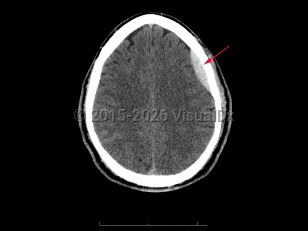

Epidural intracranial hematoma

The classic presentation involves a brief post-traumatic loss of consciousness, then several minutes to hours of a lucid interval, followed by obtundation and focal neurologic deficits. While this classic clinical description is widely taught, it is seen in < 20% of cases. Other less specific signs and symptoms include headache, nausea and emesis, seizures, neurologic deficits (contralateral weakness, hyperreflexia), papilledema, pupil-involving third-nerve palsy, somnolence, or coma.

Look For